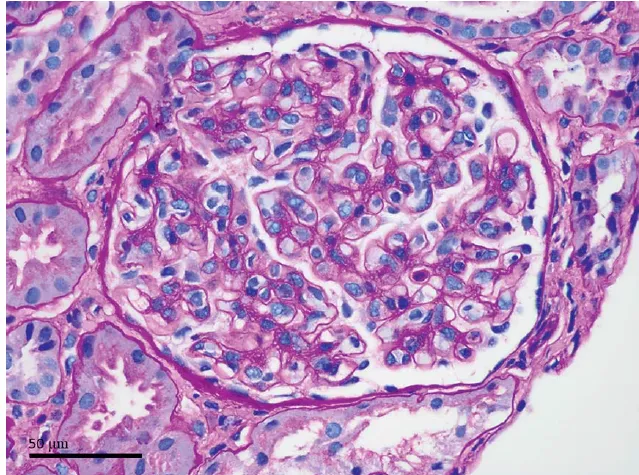

Os achados da TC sem contraste revelaram rins aumentados de tamanho, múltiplos cistos renais e nefrocalcinose (Figura 1).

Os achados tomográficos com contraste mostraram um aspecto de "buquê de flores" na fase excretora (Figura 2).

A síndrome de Beckwith-Wiedemann é uma das causas do rim espongiomedular, que se apresenta comachados específicos na tomografia computadorizada, incluindo nefrocalcinose medular, dilatação cística e um padrão de estrias semelhantes a buquês de flores nas papilas renais.